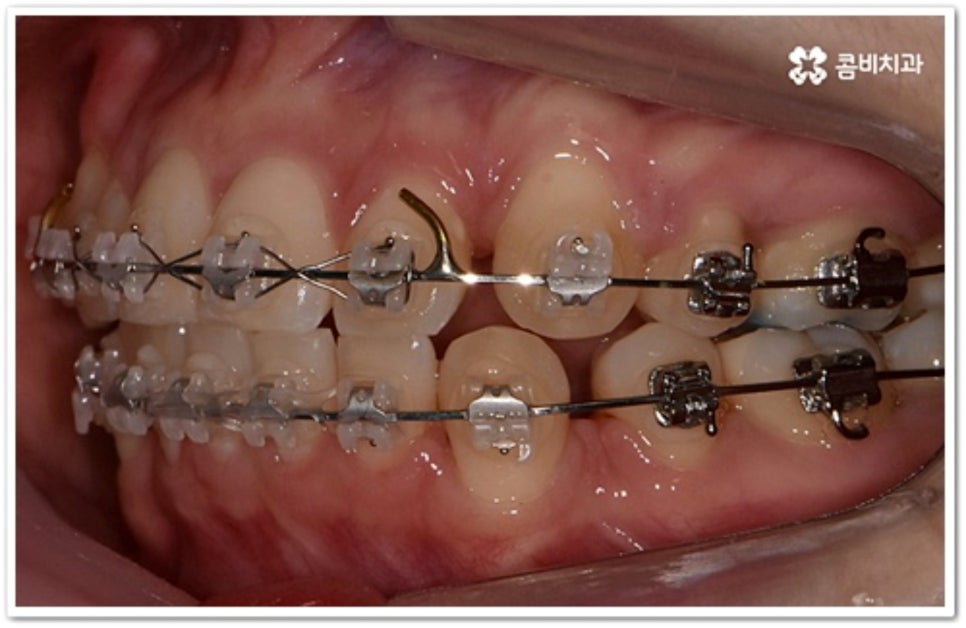

그러나 만약 덧니가 많고 부정 교합 정도가 심하거나 치아가 고르게 배열될 공간이 크게 부족하다면 덧니 발치 교정 치료를 진행하게 되는데, 이때 보통 치아 중에 기능이 가장 적은 소구치를 우선적으로 발치하게 되지만 (사진에서 확인할 수 있는 케이스) 환자분들의 상황에 따라 필요 없는 사랑니를 발치하고 어금니부터 뒤로 밀어 자리를 잡아주거나 충치 또는 짧아진 치근 등으로 심하게 손상된 치아가 있는 소구치를 우선적으로 발치하여 교정 치료를 진행하기도 하고, 필요시 임플란트와 병행하여 치료를 진행하는 경우도 있습니다. 따라서 먼저 자신의 상황에 대해서 면밀하게 검진을 받아보고 자세한 치료 계획에 대해서 의료진과 충분하게 상담해 보시는 게 좋을 거예요.

본 포스팅의 치료 케이스는 약 22개월의 치료 기간이 소요되었으며,

개인에 따라 출혈 및 부작용이 발생할 수 있고,

환자마다 치료 결과 및 기간이 상이할 수 있으므로,

정확한 치료 기간 및 치료 계획은

가까운 치과에서 상담을 받아보시길 권장 드립니다.